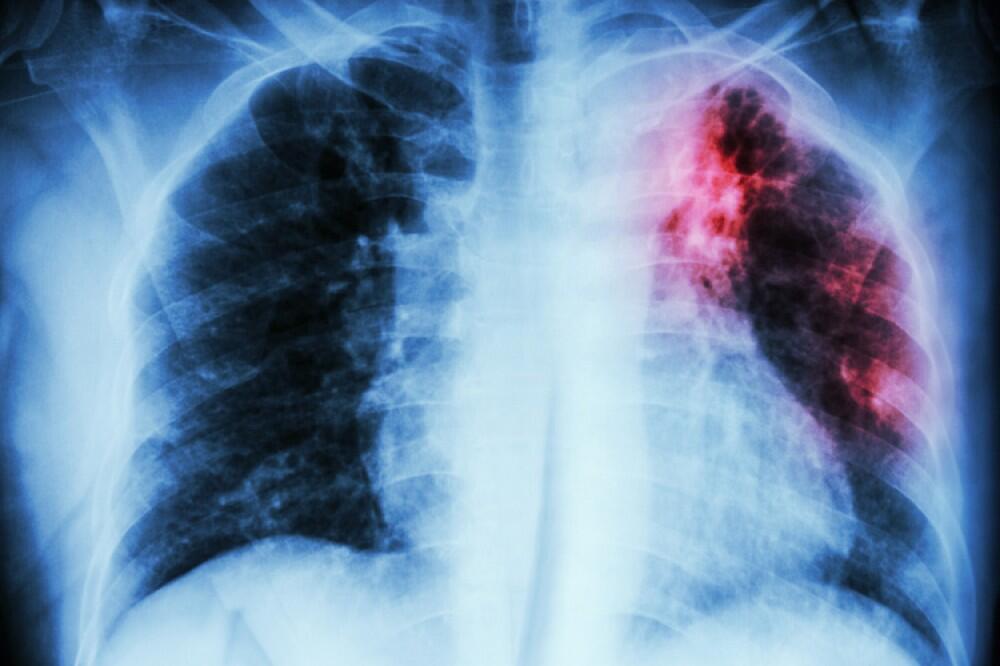

Azərbaycanda vərəmlə xəstələnmə dinamikası (100.000 əhaliyə): 2015 ildə bu göstərici 41.1 olan halda, 2025 ildə - 21,5 qeyd olunub.

Azərbaycanda ilkin ağciyər vərəmli xəstələr arasında TDM-nin (Turşuya Davamlı Mikobakteriya - Vərəm Mikobakteriyası) aşkar olunması dinamikası 2015 ildə 53% olduğu halda, 2025 ildə bu göstərici 86% çatıb.

"Həm həssas, həm də Dərmanlara Davamlı Xəstələrin müalicə göstəriciləri daha yüksək olub. Uşaq və yeniyetmələrin vərəmlə xəstələnmə göstəriciləriləri əhəmiyyətli dərəcədə yaxşılaşıb. Əgər 2015 ildə ölkədə 369 uşaq və yeniyetmə vərəm ilə xəstəlinmişdisə, 2025 ildə xəstələnən uşaq və yeniyetmələrin sayı 198 olub. Hətta 2024 il üçün bu göstəriçi 278 idi, bu da əhəmmiyətli dəyişiklik olduğunun sübutudu".